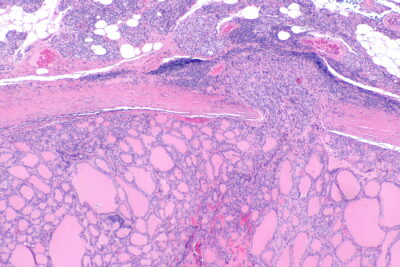

Bu gruptaki hastalar daha çok 40-60 yaş arası kadınlardır. Tiroid kanserlerinin %5 ini oluştururlar. Folliküler kanserler tiroid kanserleri içinde tanısı en zor konan gruptur. Zira bu grupta gerek ameliyat öncesi yapılmış olan ince iğne biyopsisinde gerek ameliyat sırasında yapılan dondurarak hızlı inceleme (frozen section) de lezyonun bir kanser olup olmadığını anlamak mümkün değildir. Zira bu türde kanser olup olmadığı ancak normal yapıdaki hücrelerden oluşan bu kitleyi çevreleyen kapsülün herhangi bir yerinde hücrelerin bu kapsülü delip dışarı çıkıp çıkmadığının görülmesi ile konabilir. Kapsülün bu şekilde bir istilası durumunda folliküler kanser, kapsülün sağlam kalması halinde iyi huylu folliküler adenom tanısı konur.

Tedavileri papiller tipte olduğu gibi total tiroidektomi ve istila yapmış kanser durumunda tümör büyüklüğü ne olursa olsun ameliyat sonrası radyoaktif iyot tedavisi şeklindedir. Hastaların % 80 i başarılı bir tedavi ardından normal sağlıklı yaşamlarını sürdürürler.